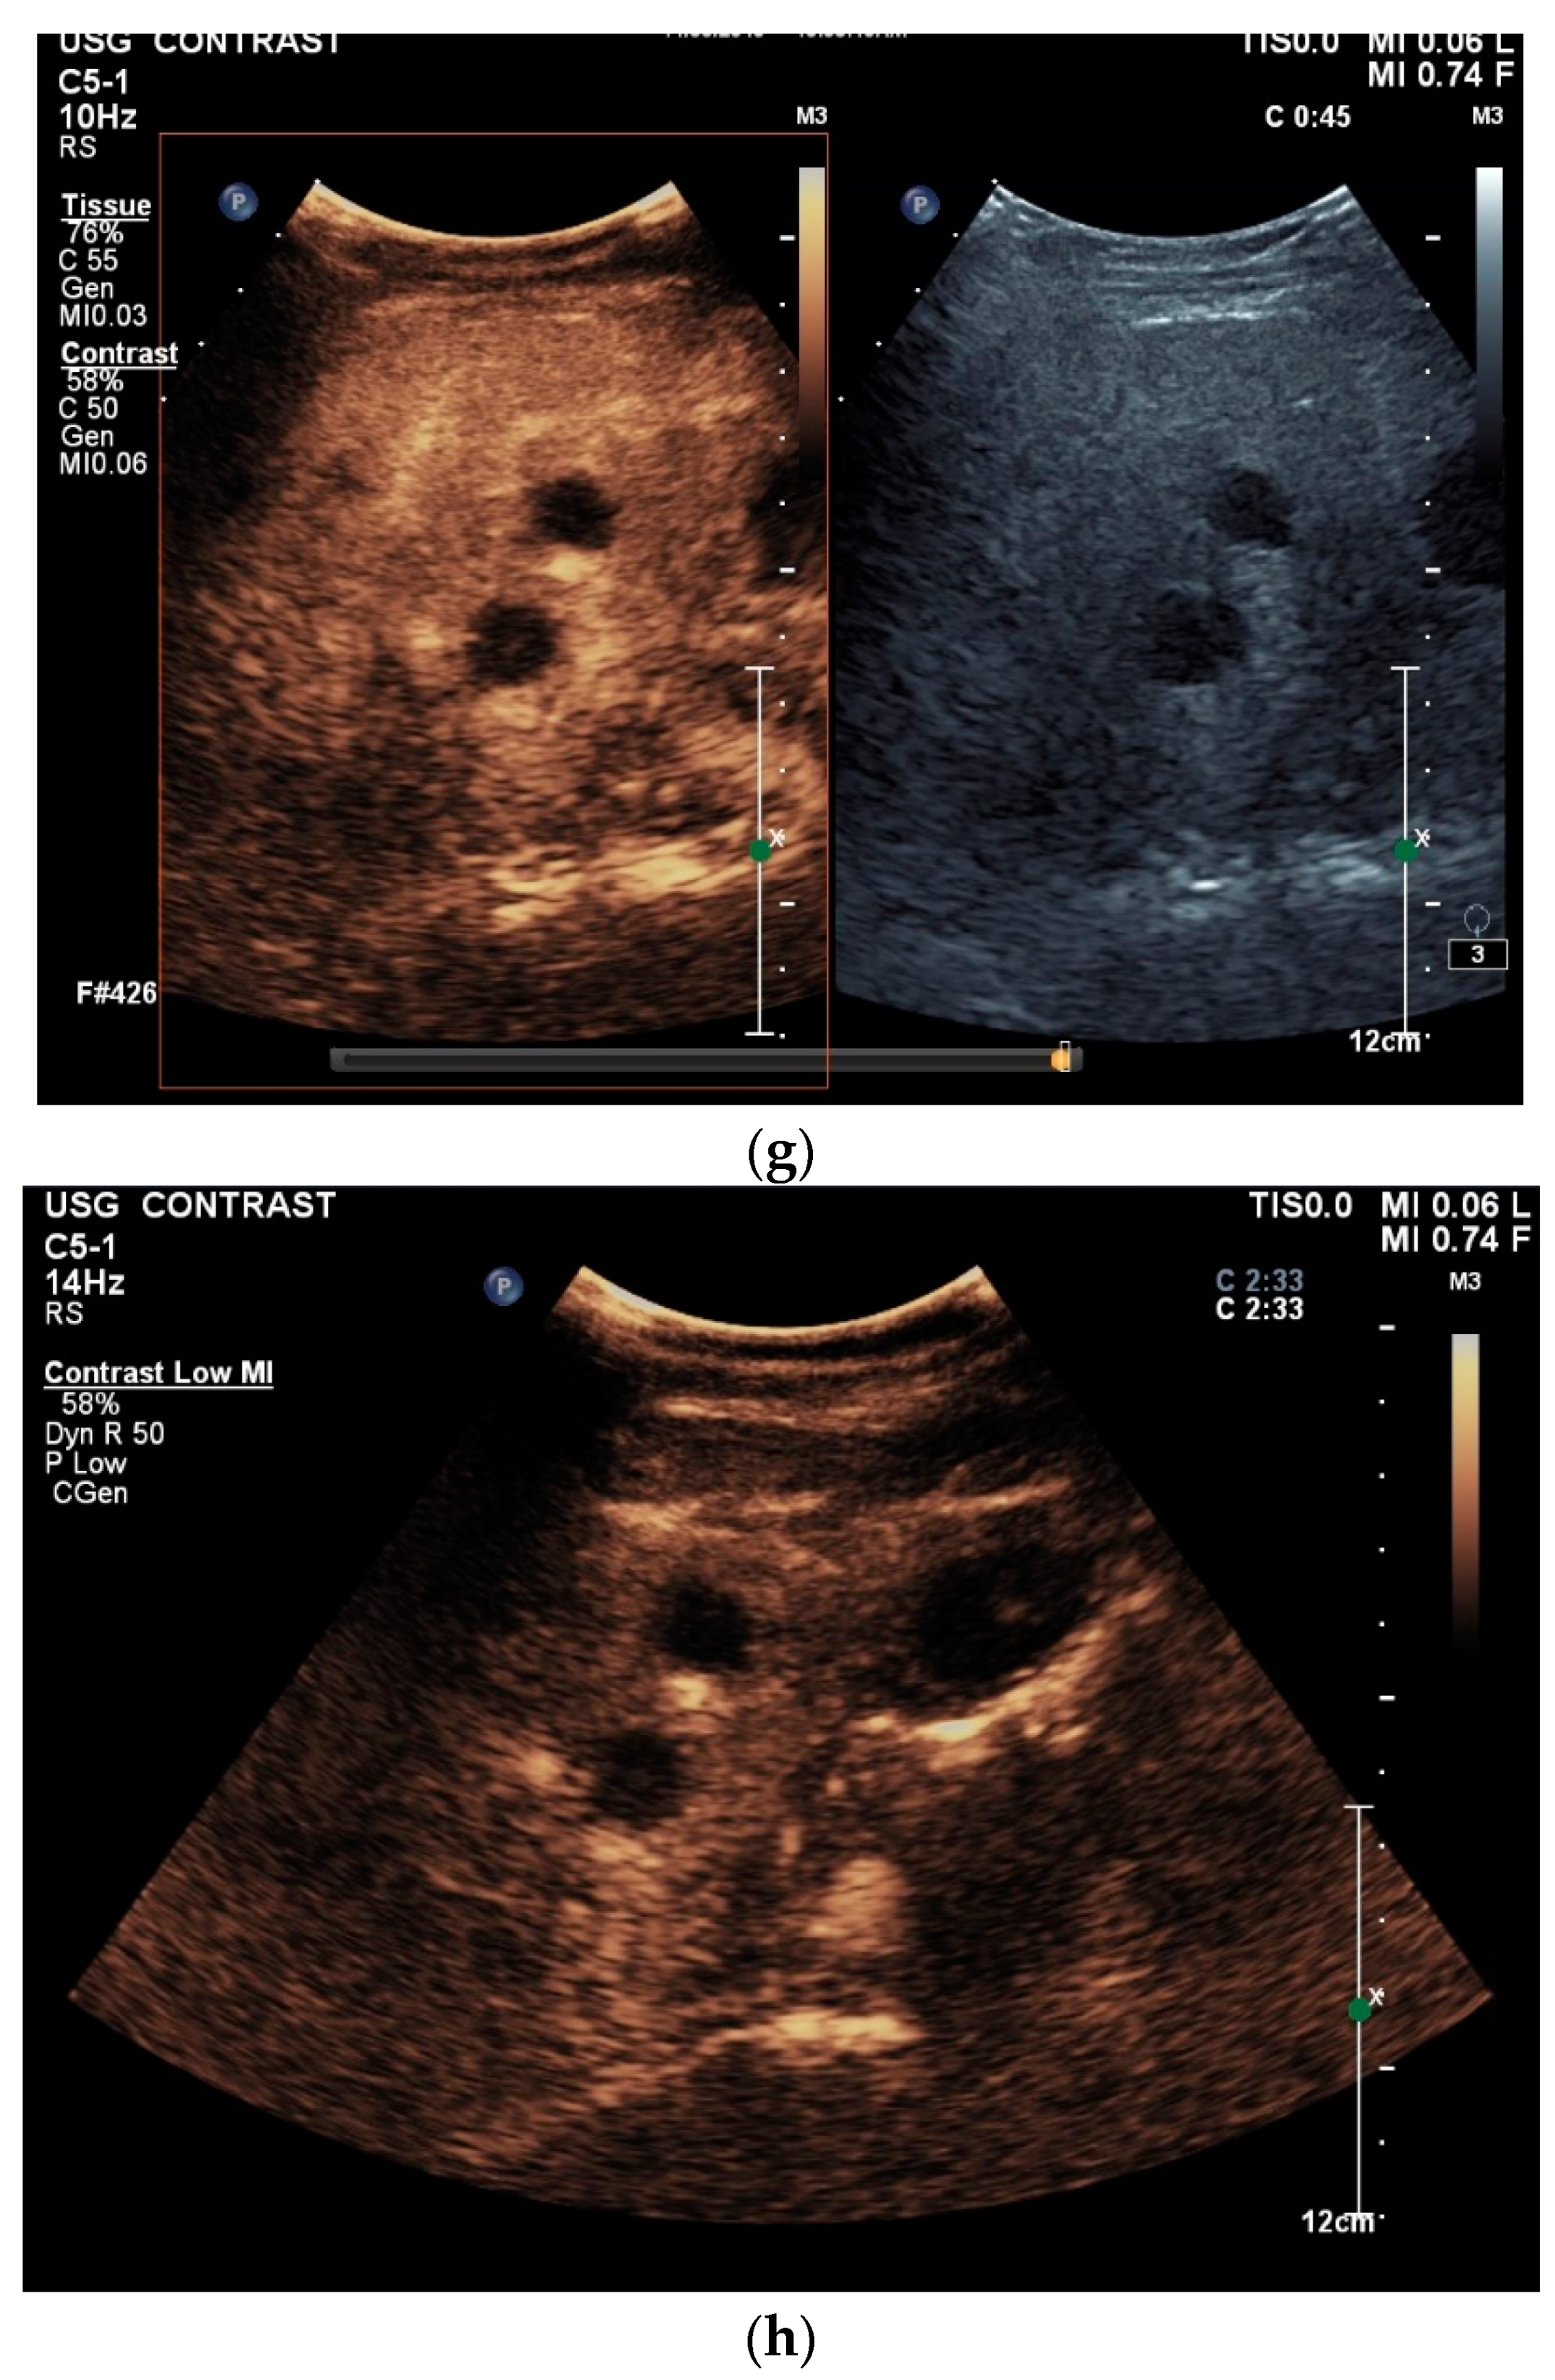

What can be seen sonographically? Ascites can be either diffuse or focal type [Figure 1a,b]. Due to the protein and cell content, these tend to be echogenic, rather than non-echoic. Attention must be paid to enlarged lymph nodes at the same time. Any thickening of the peritoneum and mesentery must be specifically searched for. This also applies to macronodular changes in the peritoneum and mesentery [Figure 1c–h]. The smallest speck-like deposits are usually not visible on ultrasound [36]. With ascites, it may be possible to observe the adhesions [31,37]. Kumar et al. were able to histologically detect granulomatous inflammation in 17/19 (89%) patients using ultrasound-guided needle biopsy of omental thickenings. In a country like India, the authors interpreted this as a manifestation of tuberculosis [32].

Figure 1.

Typical changes in the peritoneum, mesentery, and omentum in patients with tuberculosis. Ascites with pronounced septa (a). Ascites encapsulated between the abdominal wall and colon (b). Omental thickening with non-echoic caseous abscesses and few echogenic contents (c); hypoechoic nodules in hyperechoic thickened peritoneum (d). Significantly thickened hyperechoic peritoneum in B-mode US (right side of image) (marked with arrows). In CEUS, the thickened peritoneum is contrast enhanced in the arterial phase (e). In the parenchymal phase, it shows a decrease in enhancement (f). The thickened hyperechoic peritoneum shows a non-echoic lesion (arrow) (g). In the CEUS, this is not enhanced and instead shows a hyperenhanced rim. This corresponds to caseous necrosis (h).